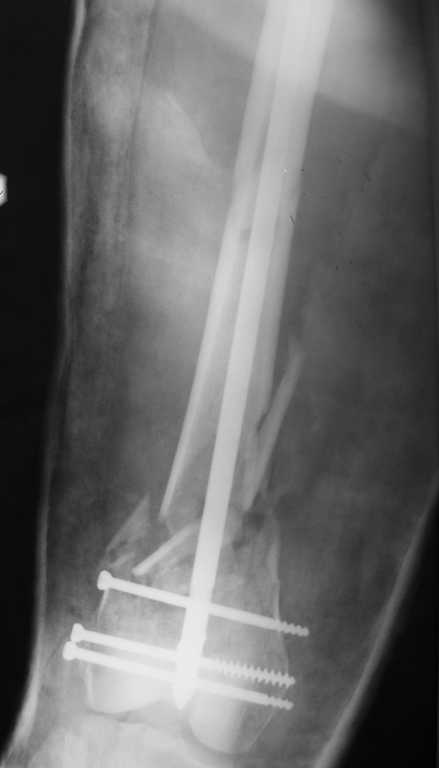

Приносим извенения за недостаток информации. Выкладываю все снимки. Стержень фирмы НПО ДЕОСТ(г.Пущино-на-оке)

И вообще мне кажется, что представленный ОС не допустим:1. стержень в суставе,2. неправильная длинна винтов, 3. ось конечности неправильная, 4. циркулярная гипсовая повязка после ОС?????

-1. стержень в суставе,

Это не критично, в межмышелковой борозде,не на опроной поверхности, выступает из субхондральной кости, не факт что из хряща.Про надколенник Александр Николаевич уже писал.

-2. неправильная длинна винтов,

и толщина тоже. При такой длине хочется помощнее.

Вполне прилично. Если в боковой проекции рекувации нет. Где кстати боковая, хочется спросить у постмейкера.